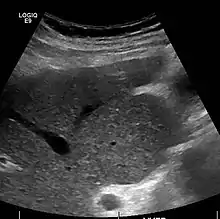

Caudate lobe hypertrophy on ultrasound due to cirrhosis

Imaging

Ultrasound is routinely used in the evaluation of cirrhosis.[34] It may show a small and shrunken liver in advanced disease. On ultrasound, there is increased echogenicity with irregular appearing areas.[51] Other suggestive findings are an enlarged caudate lobe, widening of the fissures and enlargement of the spleen.[52] An enlarged spleen, which normally measures less than 11–12 cm (4.3–4.7 in) in adults, may suggest underlying portal hypertension.[53] Ultrasound may also screen for hepatocellular carcinoma and portal hypertension.[34] This is done by assessing flow in the hepatic vein.[54] An increased portal vein pulsatility may be seen. However, this may be a sign of elevated right atrial pressure.[55] Portal vein pulsatility are usually measured by a pulsatility indices (PI).[54] A number above a certain values indicates cirrhosis (see table below).